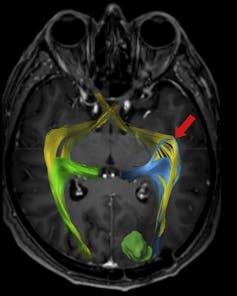

Imagen tractográfica del sistema visual.

Bertani et al., 2018

Podría parecer que, en el cerebro, cada región se dedica a una cosa. Sí y no. Hay regiones que realizan funciones concretas, por ejemplo, en el sistema visual.

Cada parte de nuestro campo visual está ordenada en las conexiones hasta nuestra corteza visual primaria, en la nuca. Imaginemos que miramos la esfera de un reloj de saetas, una lesión concreta en esta vía puede provocar que dejemos de ver nuestro campo visual entre las 9 y las 12. Más allá de la corteza visual primaria, la información se procesa en distintas áreas para identificar lo que vemos a partir de lo que ya sabemos y la cosa es mucho más complicada.

El cerebro, en realidad, funciona como un todo siempre activo. Sus conexiones solo se pueden tratar de comprender desde un enfoque holístico, de ahí el término “conectoma”.